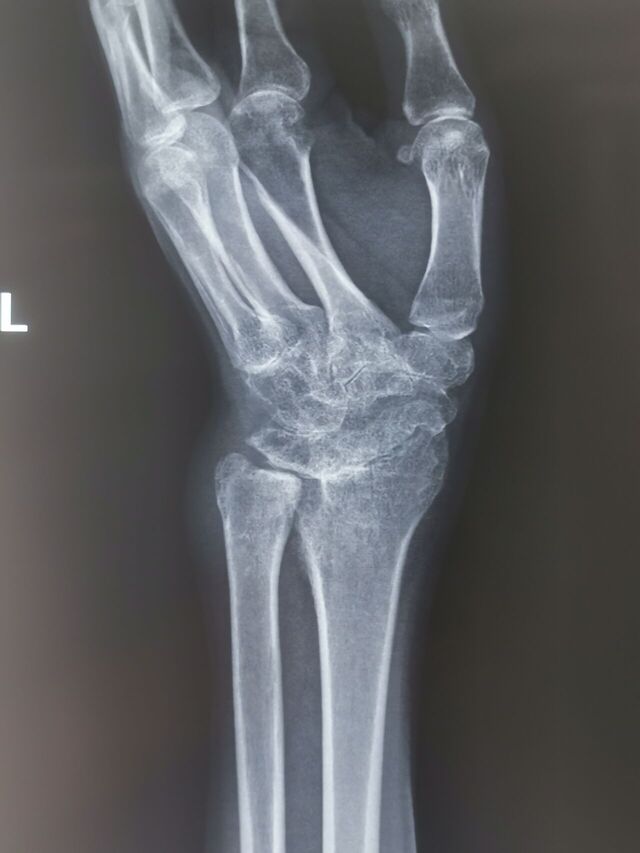

陈旧性月骨周围脱位,创伤性关节炎,下尺桡不稳

IMG_20231025_095800.jpg

IMG_20231025_095755.jpg

IMG_20231025_095748.jpg